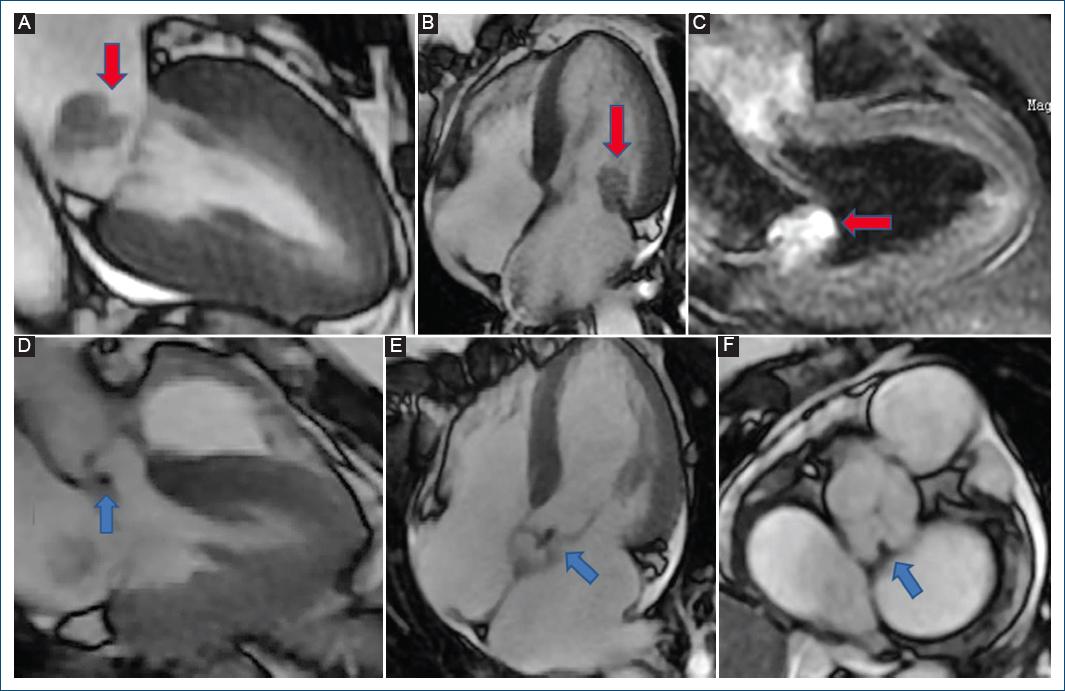

Fue derivada desde su ciudad de residencia por diagnóstico de posible endocarditis mitral, presentando pérdida de peso y sudoración nocturna de cuatro meses de evolución, descripción de una vegetación en valva posterior mitral y seis hemocultivos negativos. En nuestra institución se realizó ecocardiograma transtorácico, que evidenció masa móvil homogénea de 22 x 18 mm adherida a la valva mitral posterior de posible origen tumoral con protrusión hacia ventrículo izquierdo y generando insuficiencia mitral moderada (Fig. 1). No presentaba alteraciones en el electrocardiograma o el laboratorio. Se efectuó resonancia magnética (RM) cardiaca que informó la presencia de una masa en anillo mitral posterior de 20 mm hipervascular con captación y retención de contraste, y otra lesión similar pequeña en válvula aórtica (Fig. 2). Ante la sospecha de metástasis cardiaca, se realizó tomografía computarizada (TC) de abdomen y pelvis que detectó una masa isodensa heterogénea de 32 x 30 mm en el polo renal inferior derecho con necrosis interna y captación de contraste periférico, y un nódulo heterogéneo hipercaptante de 20 x 18 mm en glándula suprarrenal izquierda, ambos de origen neoformativo (Fig. 3). Se realizó TC de tórax que evidenció una masa hipercaptante subpleural a nivel basal posterior izquierdo de 29 x 28 mm que infiltraba los tejidos blandos y músculos intercostales adyacentes, además de múltiples nódulos pulmonares de hasta 5 mm compatibles con secundarismo (Fig. 3). La TC de encéfalo resultó normal. Se realizó RM de abdomen con contraste que detalló que la masa renal era compatible con neoplasia primaria y que el nódulo suprarrenal era compatible con secundarismo (Fig. 3). Se realizó biopsia renal, de una lesión pulmonar y de las subpleurales, compatibles con un carcinoma renal papilar de células claras con inmunohistoquímica positiva para vimentina y citoqueratina 7 en forma difusa y con patrón cup-like con anhidrasa carbónica IX. Se interpretó como carcinoma renal avanzado, con metástasis cardiacas mitral y aórtica (sin invasión de la vena cava), pulmonares, subpleurales y suprarrenal contralateral.

Figura 2 Resonancia magnética cardiaca. Se observa una metástasis adherida a valva posterior mitral (flechas rojas) en sístole (A), diástole (B) y en diástole y con retención de contraste (C). También se observa una metástasis pequeña adherida en cara ventricular de válvula aórtica (flechas azules) en eje largo de tres cámaras (D), eje largo de 5 cámaras (E) y eje corto (F).